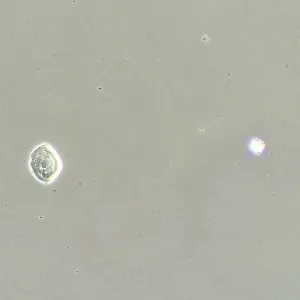

Фазово-контрастная микроскопия позволяет увидеть детали прозрачных образцов, которые практически не видны в светлом поле, и при этом не повреждать их окрашиванием. Метод применяют в разных сферах: медицине, биологии, ветеринарии, сельском хозяйстве, фармацевтике, экологии.